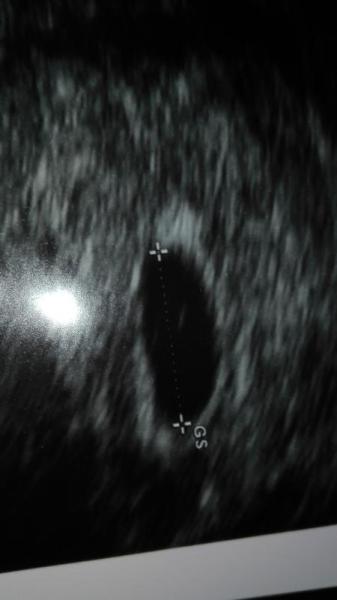

Bin sehr froh das man heute schon die Fruchthöhle gesehen hat, denn eigentlich dachte Ich das heute 5+4 SSW ist, er hat mich aber zurück datiert in die 5ssw weil man noch keinen Herzschlag oder Ähnliches gesehen hat...

Aber soweit alles in Ordnung und das ist ja die Hauptsache!

Komisch fand ich nur als er mir sagte wenn man genau hin schaut sieht man auch schon den Inhalt. Ich allerdings sehe dort zwei Punkte, oder täusche ich mich?! Was seht ihr?

Zwillinge wäre ein Traum

Nächsten Freitag hab ich den nächsten Termin, hoffentlich wird es dann eindeutig sein *hibbel*

Ich glaub ich habe das falsche Bild genommen, hier nochmal:

ahhhhhhhhhhhh aslo auf dem seh ich jetzt nur 1 auch. lassen wir uns mal überraschen beim nä termin